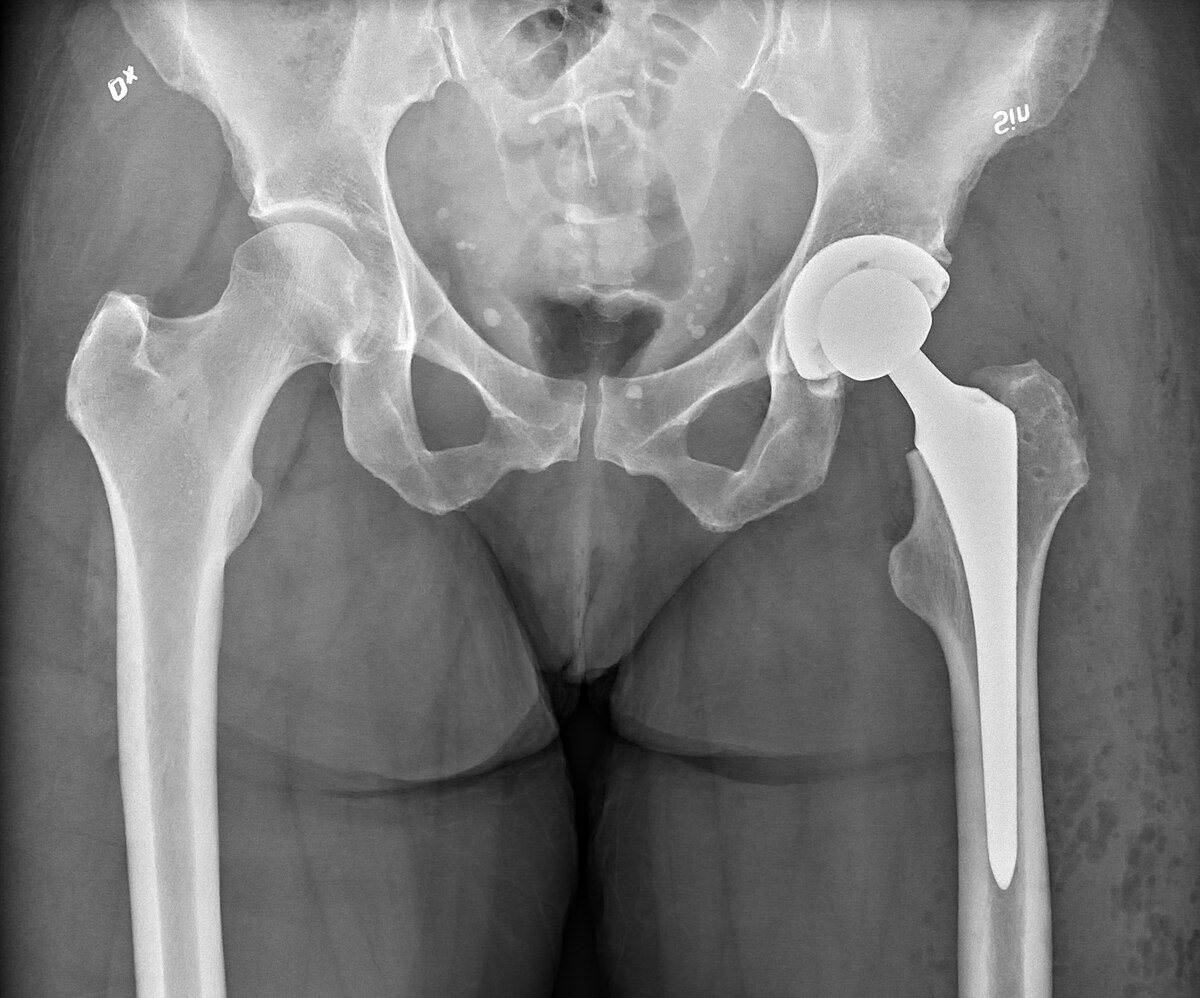

Hip replacement, or hip arthroplasty, is a surgical procedure where a damaged or arthritic hip joint is replaced with a prosthetic implant. This procedure is recommended for individuals suffering from chronic hip pain due to arthritis, sports injuries, or degenerative conditions. Dr. Lokesh Yogi and his team at Jaipur Ortho are leaders in minimally invasive hip replacement surgery, offering precise treatment plans for faster recovery and long-term success.

- Total Hip Replacement (THR): Replacement of both the ball and socket of the hip joint.

- Revision Hip Replacement: Surgery to replace or repair a previous hip implant.